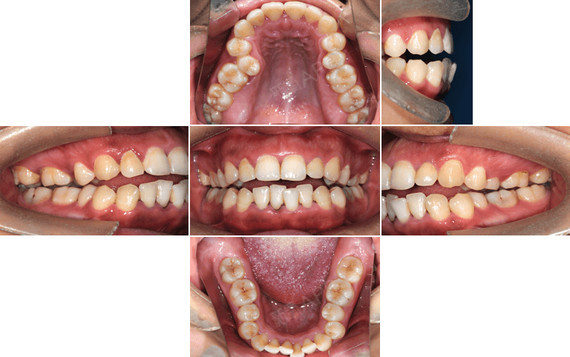

从他的照片和x光片可以看出面型是明显的上牙突出,嘴巴突出,下巴后缩

嘴突下巴后缩是需要正畸还是正颌为什么有些人正畸后下巴改变会那么大